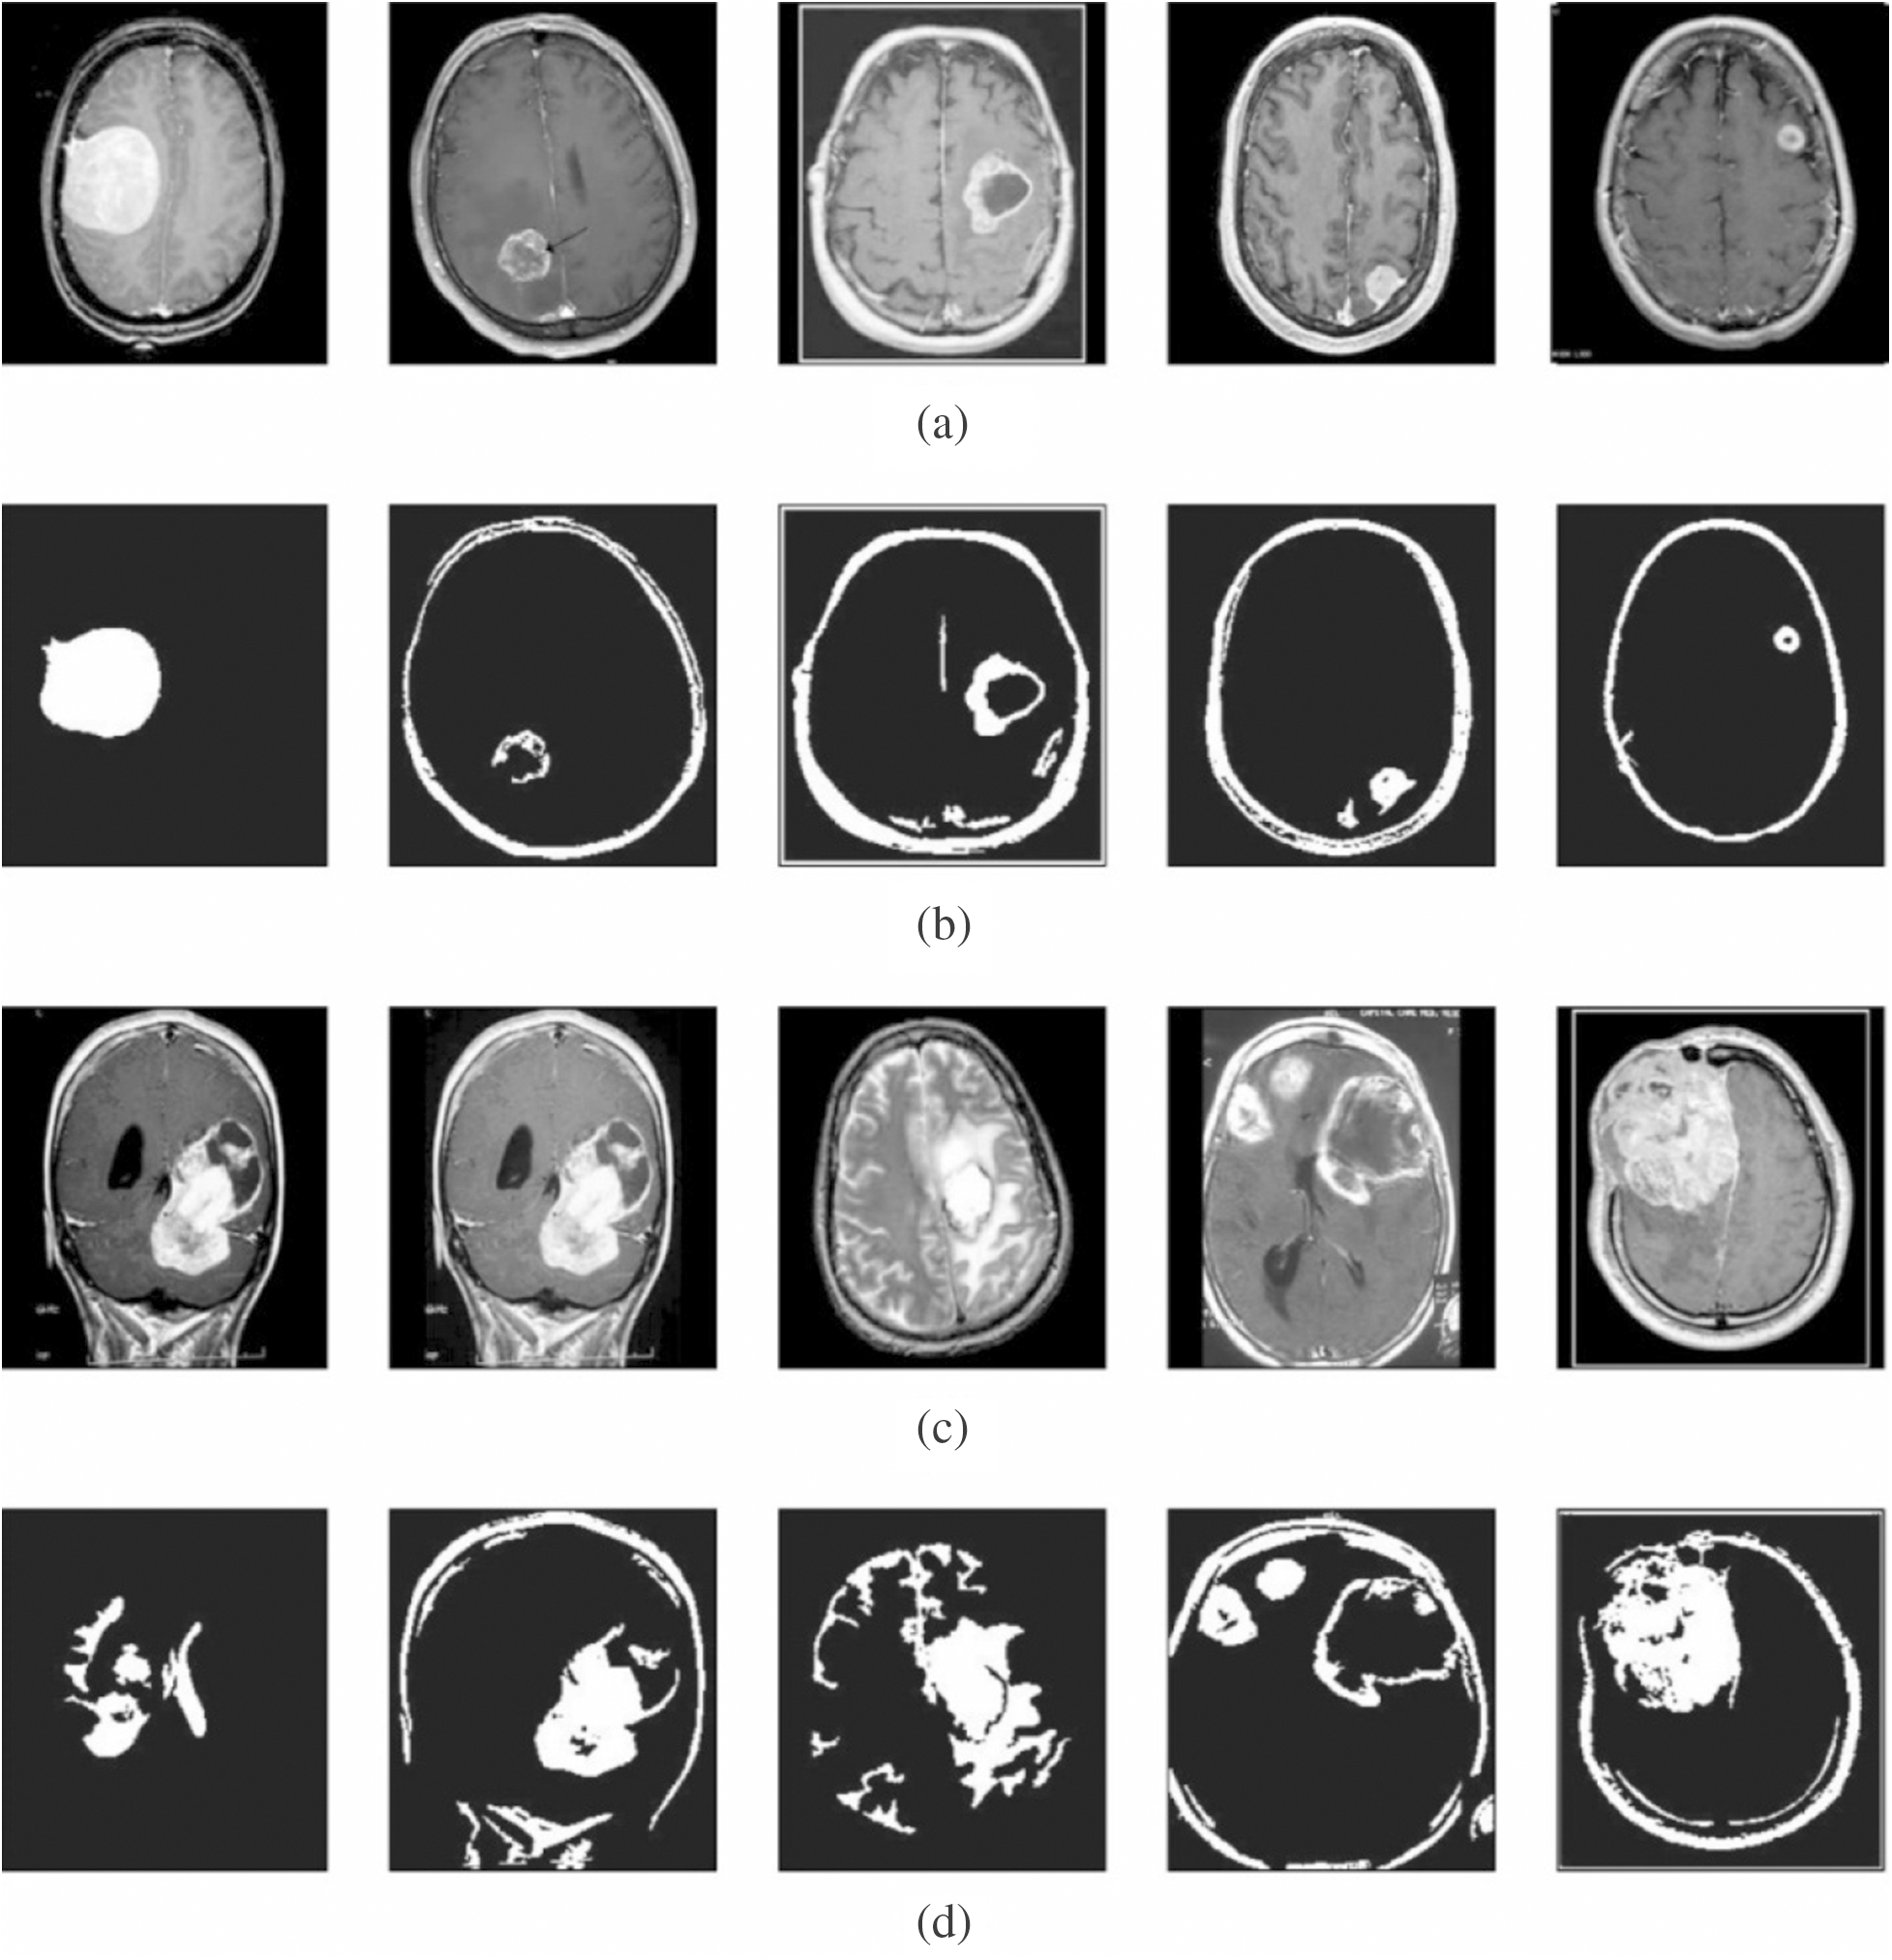

Next, Fig. 4 shows the resultant images from the segmentation process. The first and third rows indicate the contrast-enhanced images, whereas the corresponding segmented images are provided in the second and fourth rows. The figure clearly states that the images are properly segmented using the presented model.

Figure 4: Visualization of segmentation results. (a) and (c) Contrast enhanced image. (b) and (d) Segmented image